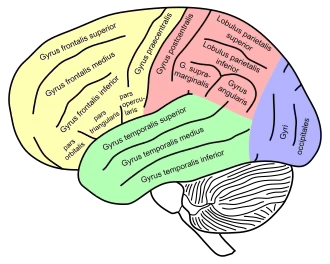

Lateral surface of left cerebral hemisphere, viewed from the side. (Middle temporal gyrus shown in orange.) | |

Middle temporal gyrus is a gyrus in the brain on the temporal lobe. It is located between the superior temporal gyrus and inferior temporal gyrus. It corresponds largely to Brodmann area 21.

The middle temporal gyrus is bounded by:

- the superior temporal sulcus above;

- the inferior temporal sulcus below;

- an imaginary line drawn from the preoccipital notch to the lateral sulcus posteriorly.

Lateral view of a human brain, main gyri labeled.

Lateral view of a human brain, main gyri labeled. -